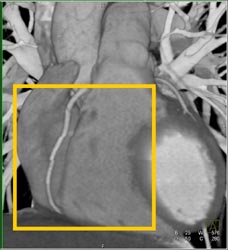

Diagnosis

Normal LAD